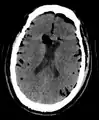

| Pneumocephalus and comminuted fracture of the frontal sinus |

Pneumocephalus is the presence of air or gas within the cranial cavity. It is usually associated with disruption of the skull: after head and facial trauma, tumors of the skull base, after neurosurgery or otorhinolaryngology, and rarely, spontaneously. Pneumocephalus can occur in scuba diving, but is very rare in this context.